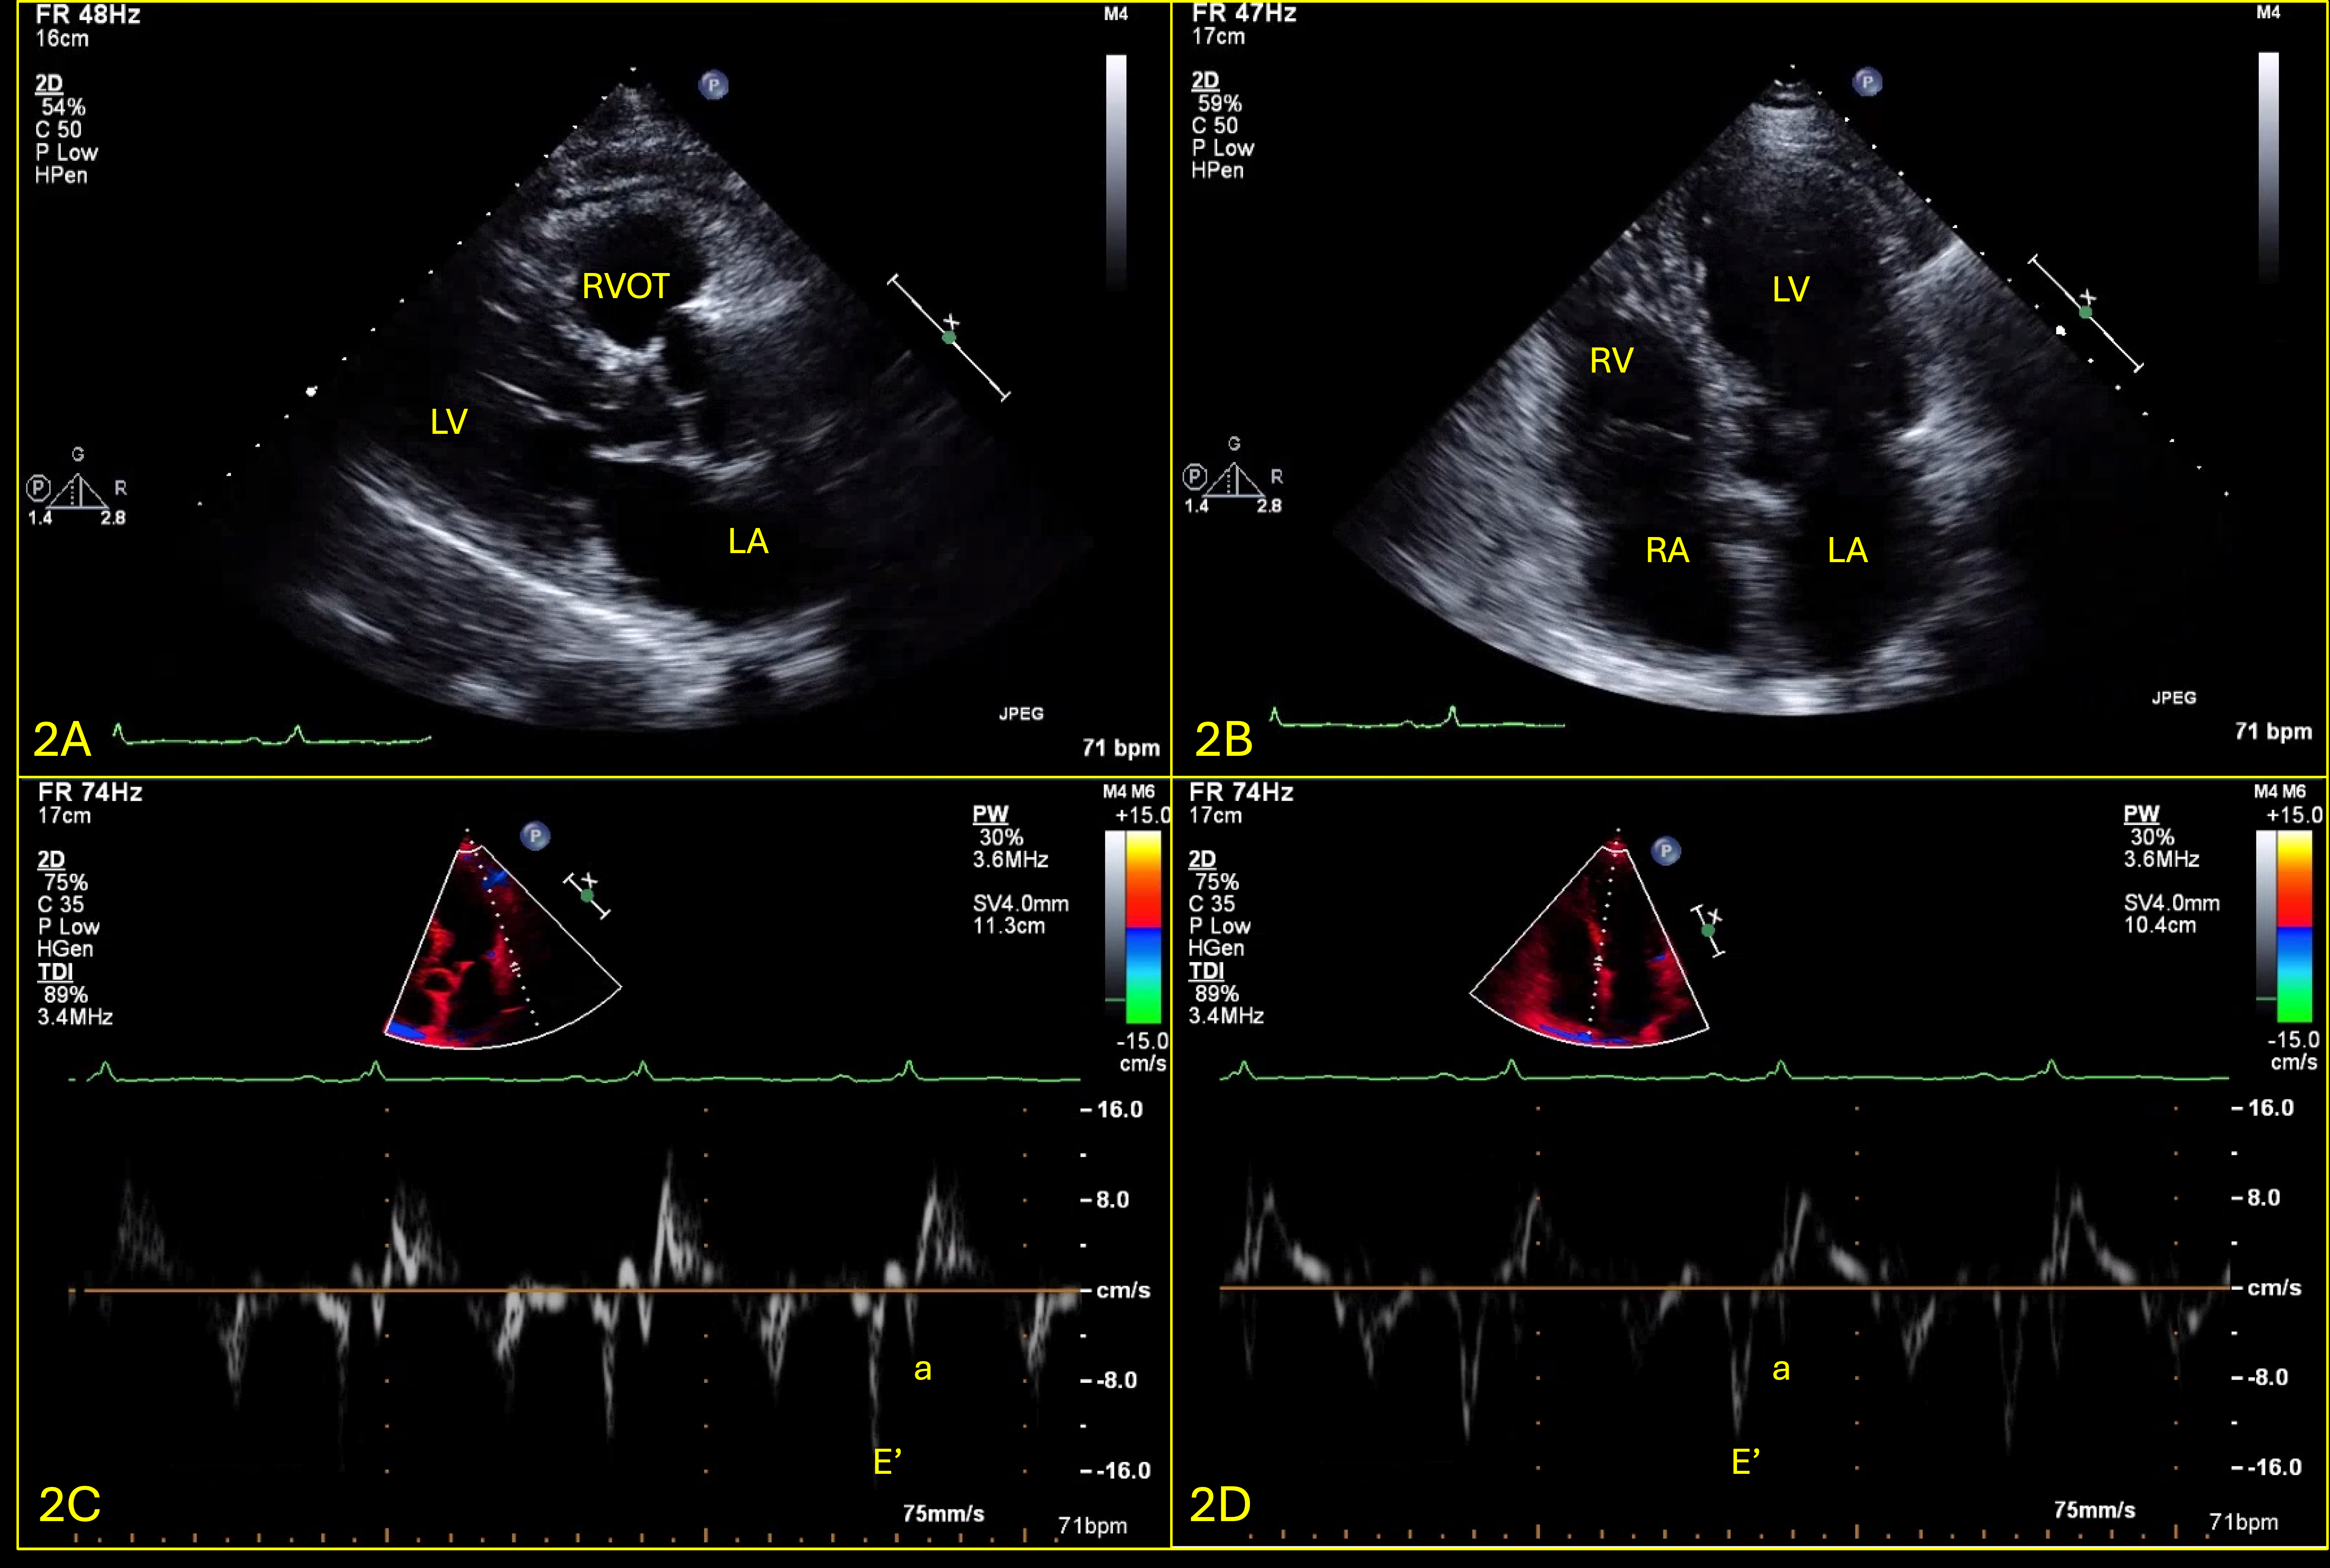

Abstract Body (Do not enter title and authors here): Case Presentation: A 76-year-old male, non-smoker, with history of HLD and NIDDM, presented with several weeks of dyspnea and cough, unresponsive to outpatient treatments. He was normotensive and found to have new onset atrial fibrillation at a rate of 110bpm and pulsus paradoxus with a difference of 15mmHg. CT chest showed a 2.2cm thyroid nodule along with a pericardial effusion (PE), confirmed to be tamponade on TTE (Fig.1). A TTE showed resolution of tamponade after the pericardial window (Fig.2). Pericardial fluid cytology was positive for malignant cells. Patient was discharged, had an outpatient PET CT which showed uptake in the thyroid, pericardial region & right supraclavicular lymph node (LN). The patient developed symptoms of heart failure, prompting his 2nd visit to the hospital after 3 weeks. A repeat TTE showed a small PE with effusive-constrictive physiology (Fig.3). He was started on high dose steroids and diuresed as tolerated, but his symptoms did not improve. He underwent thyroid nodule and right supraclavicular LN biopsy, which revealed high grade follicular thyroid carcinoma (FTC). His course was complicated by multiorgan failure, prompting transfer to another facility for pericardiectomy; during which he was found to have extensive tumor infiltration into the myocardium; he then went into shock and passed away shortly after.